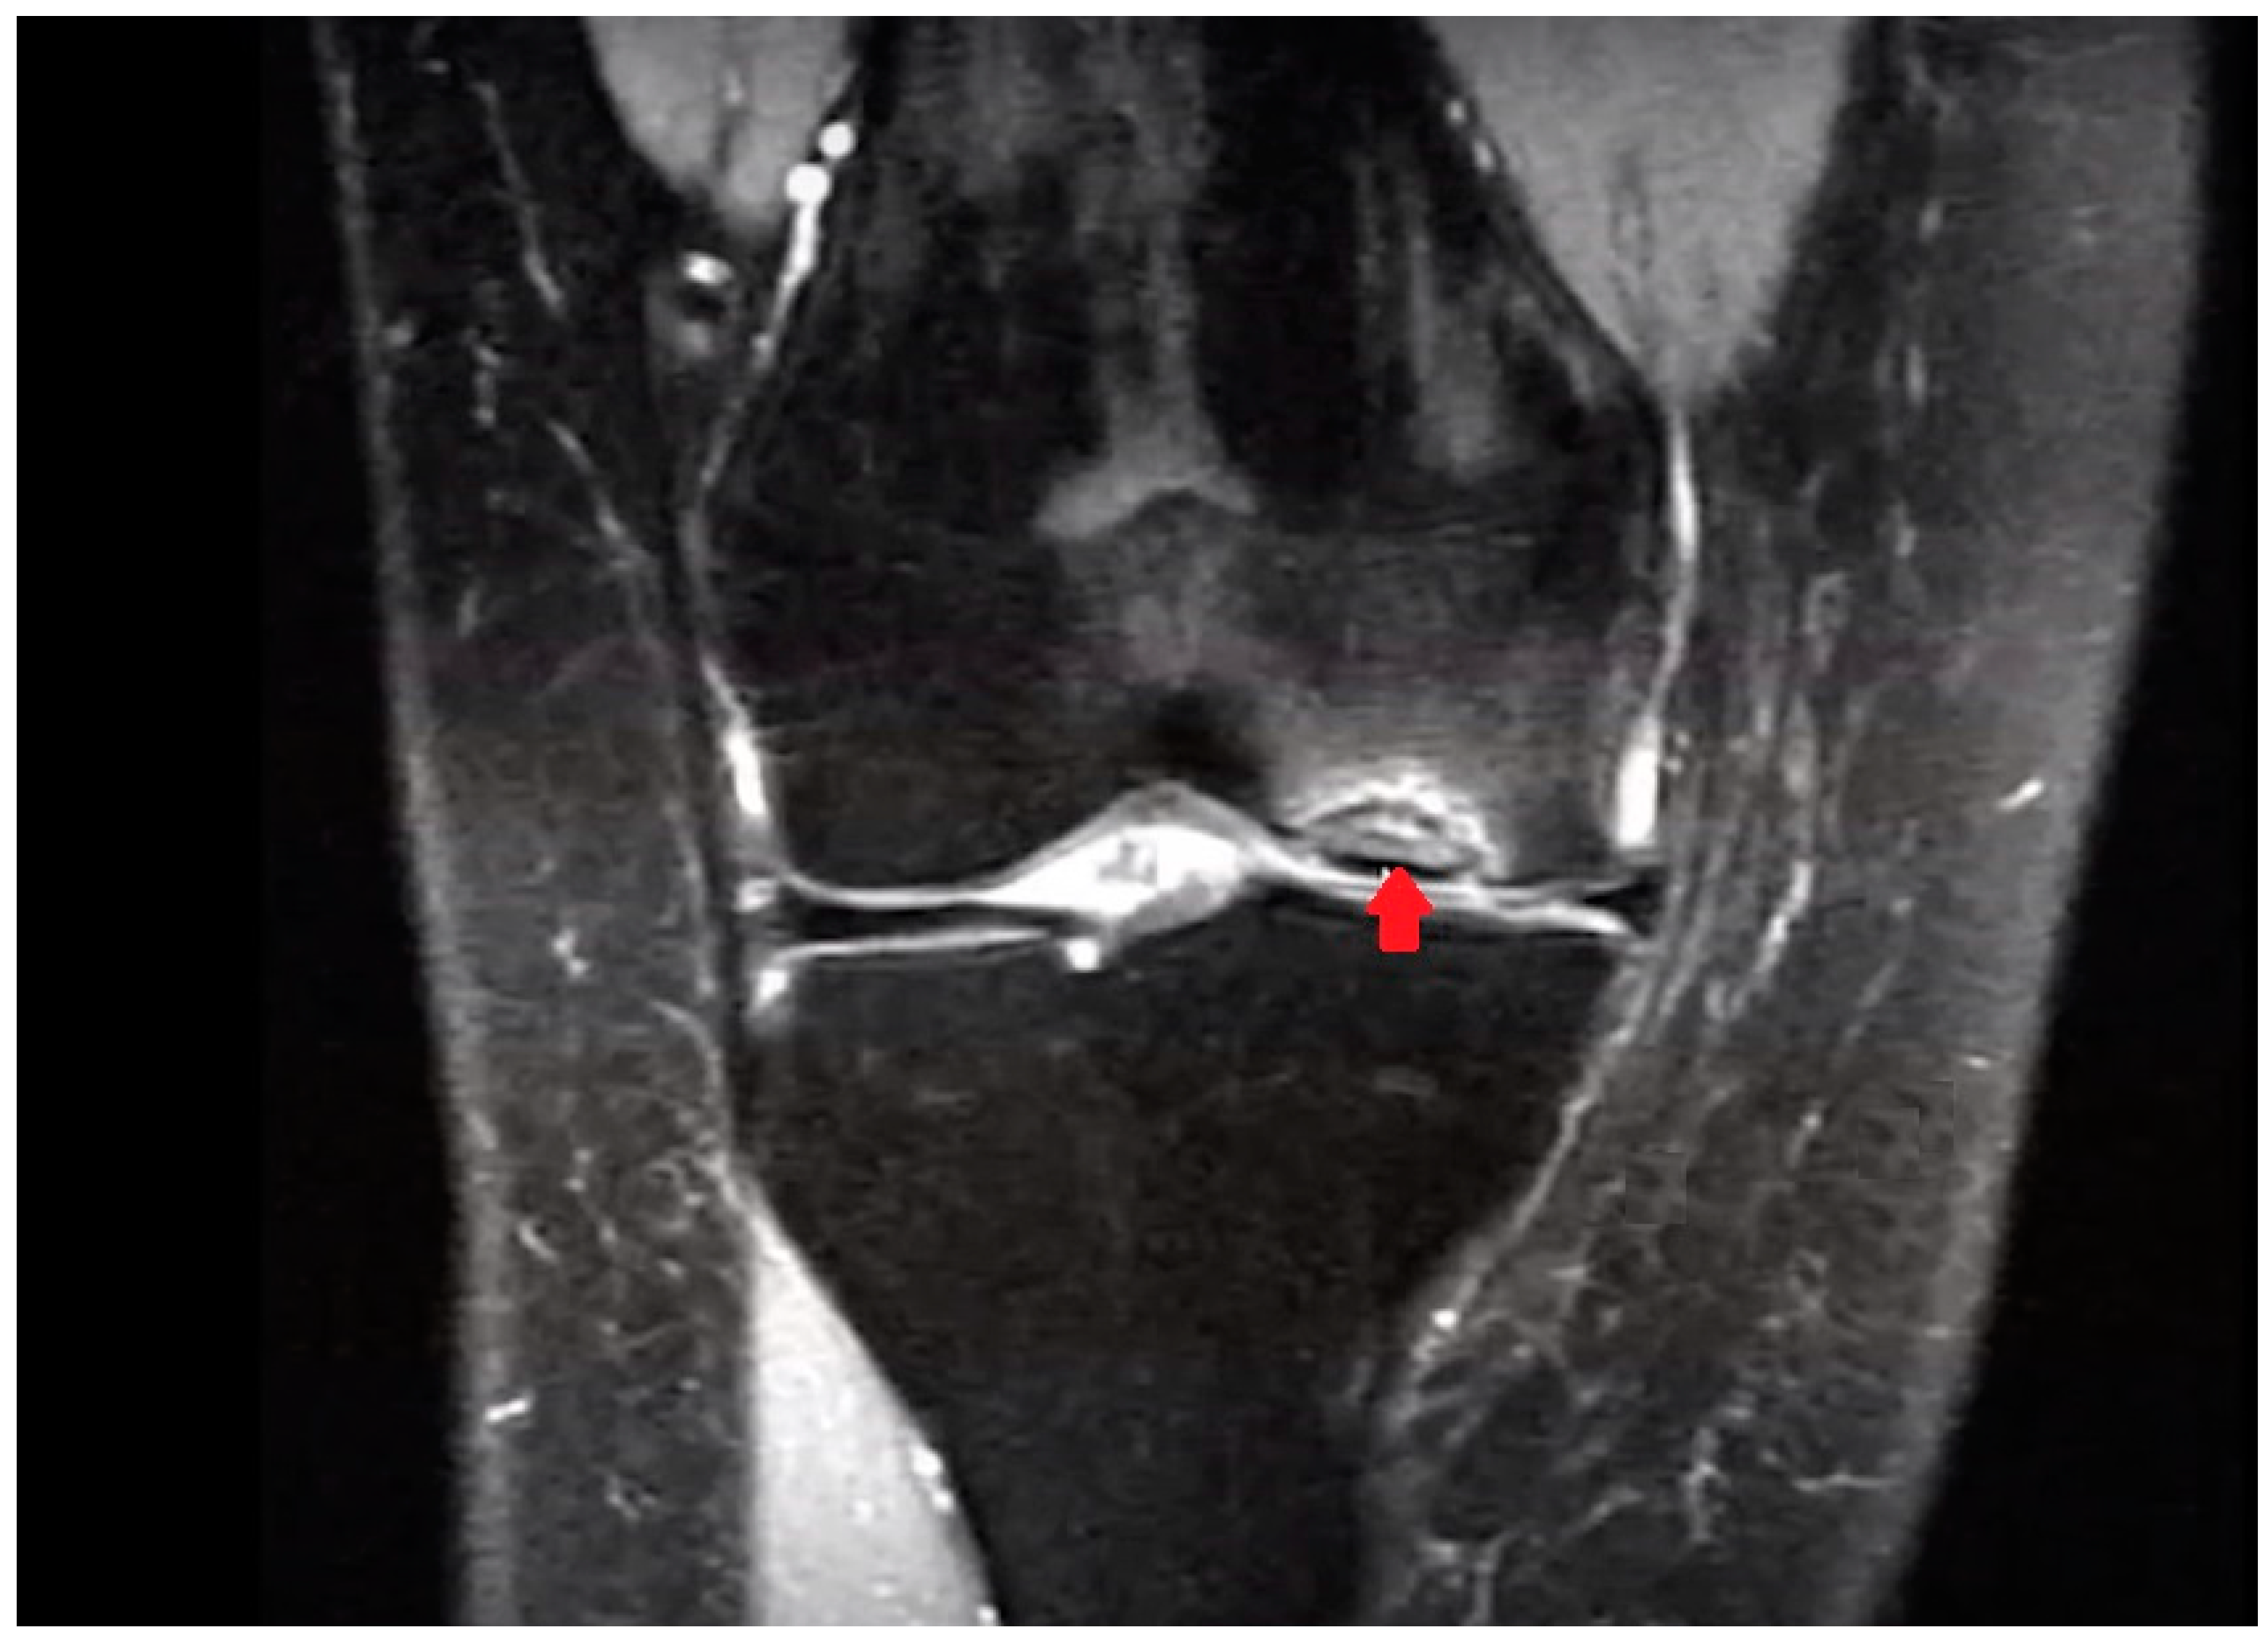

In knee OCD, the progeny typically appears hypointense on T1 MRI images and shows heterogeneous signals on T2 images (Figure 2). MRI is more effective in evaluating the volume of the lesion and may reveal an osteochondral fragment that extends beyond the normal contour of the epiphysis, a defect at the original site of the fragment, or loose fragments within the joint cavity. The “Oreo cookie sign” in MRI imagery is characterized by a curvilinear hyperintense T2 signal at the interface of the progeny and the parent bone (resembling the cream of an Oreo cookie), flanked by two layers of hypointense signals (similar to the cookie wafers). The presence of focal cysts at the interface between the progeny and the parent bone indicates a more chronic condition [40].

Figure 2.

OCD of the medial femoral condyle as seen on an MRI (coronal view, T2-weighted). The arrow indicates OCD of the medial condyle of the femur.